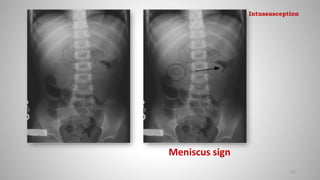

• Meniscus sign: Crescent of gas within colonic lumen that outlines the

apex of intussusceptum

Meniscus sign